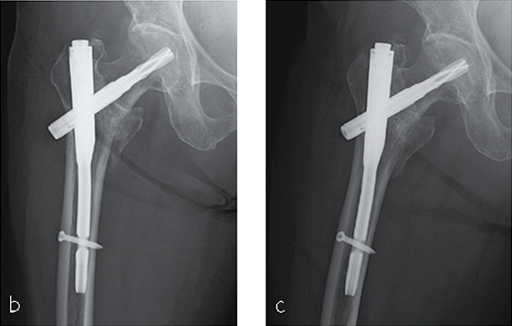

She was operated on the next day and fixed with a PFNA Asia (size: extra small, angle 130 degrees, distal diameter: 9 mm, blade length 100 mm) (Fig 6a). Good reduction and stable fixation were obtained. Full weight-bearing gait was allowed on the second postoperative day. There was an uneventful postoperative course, and good union was obtained at three months after surgery (Fig 6b).